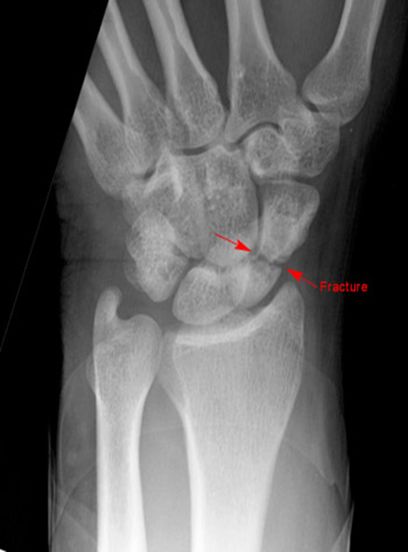

舟骨骨折

• 最常见的腕骨骨折

• 易漏诊

• 易发生缺血性坏死

• 儿童少见

疼痛科怎么理疗疼痛科医生、康复理疗科医生、针刀针灸医生应掌握的常见骨科疾病X光片_https://www.jmylbn.com_新闻资讯_第26张